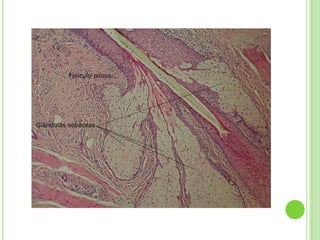

o PIEL DELGADA O FINA

Recubre la mayor parte del

cuerpo, tiene estrato córneo

delgado carece de estrato

lúcido y granuloso, tiene

folículos pilosos, músculos

erectores del pelo, glándulas

sebáceas y glándulas

sudoríparas.

ANEXOS O FANERAS

Folículos pilosos.

Glándulas sebáceas.

FOLÍCULOS PILOSOS

   Parte de la piel que da

crecimiento al cabello al

concentrar células

madre formándose a

partir de una

invaginación tubular.

GLÁNDULAS SEBÁCEAS

   Están en corion y se distribuyen en toda la

superficie cutánea.

   Las más grandes en nariz y frente.

   Productora de sebo para la protección del pelo.

   Forma capa delgada que cubre la piel e impide

evaporación y absorción excesiva.